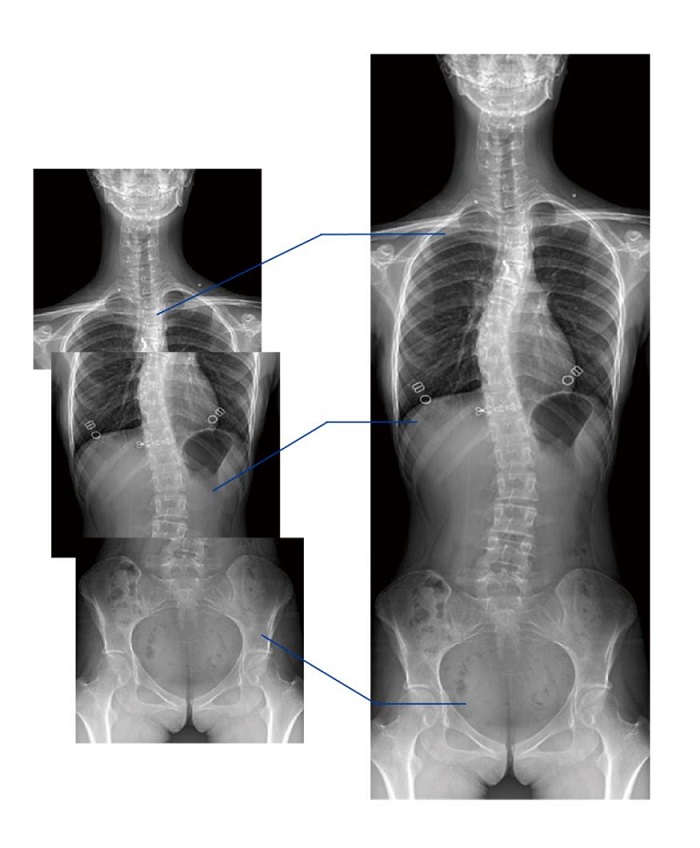

另外,動態(tài)DR的全景拼接功能,可通過對脊柱、下肢及下肢靜脈造影進(jìn)行分段攝片,然后對分段圖像進(jìn)行拼接,在一幅X光圖像上完整顯示全脊柱或下肢整體形態(tài)。對于骨科疾病患者的全脊柱、全下肢病變情況圖像展示更加具有完整性,有助于骨科疾病患者臨床診斷效果的提升。

普利德多功能動態(tài)DR將數(shù)字?jǐn)z影、數(shù)字透視、數(shù)字造影、毫秒級高清點片、影像實時保存與回放、全景拼接等多種功能集于一身。像素尺寸達(dá)到業(yè)界領(lǐng)先的100微米,率先實現(xiàn)5.0lp/mm超高分辨率成像,大幅提升細(xì)節(jié)檢測能力;透視幀率高達(dá)30幀/秒,有效避免漏診、誤診;靜態(tài)攝影有效像素高達(dá)1800萬,較之于傳統(tǒng)900萬點片像素,圖像細(xì)節(jié)更加清晰銳利,影像質(zhì)量躍升至新高度,為隱匿性肋骨骨折診斷提供至清影像,輔助醫(yī)生實現(xiàn)精準(zhǔn)診療!